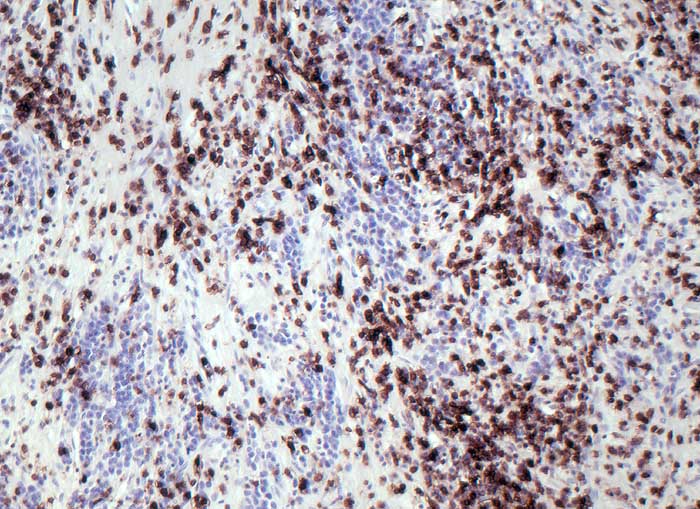

CD45 (leucocyte common antigen, LCA)

Anfärbung:

Zellmembran

Reaktion im Normalgewebe:

Fast alle haematolymphoiden Zellen sind positiv: T-Lymphozyten, B-Lymphozyten, Granulozyten, Monozyten, Makrophagen.

Reaktion in Neoplasien:

93-99% aller Lymphome sind positiv. Einzelne high grade Lymphome sind CD45 negativ und CD20 positiv.